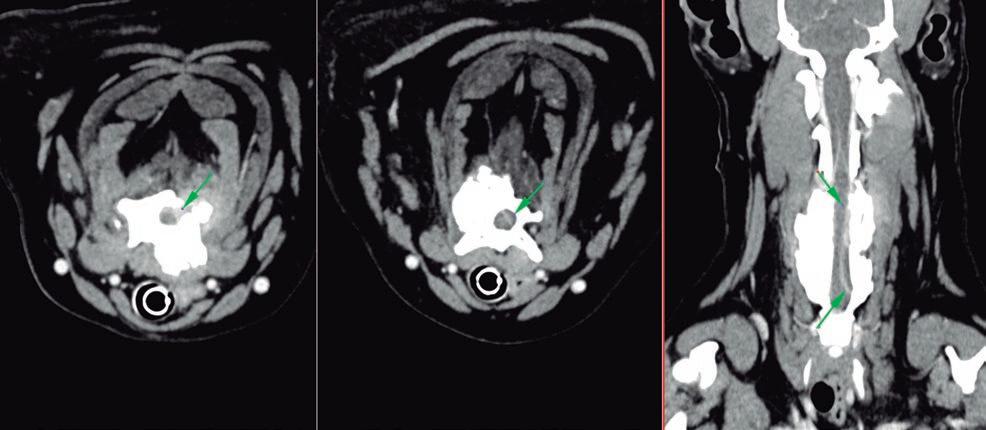

Issuu converts static files into: digital portfolios, online yearbooks, online catalogs, digital photo albums and more. Sign up and create your flipbook.